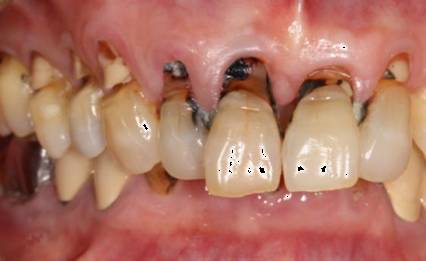

很多人觉得刷牙只不过是一件小事情,其实不然。现在,请你先对照镜子,张开嘴,看看你的牙齿根部,是不是像下图一样,隐隐约约有些凹下去了?如果是,那你就得当心了!

与普通蛀牙不同,出现这种情况,你的牙齿危险了!医学上称之为“楔状缺损”!

这种横槽就是“楔状缺失”!由于它外形酷似木匠用的楔子,因此称为“楔状缺损”。

楔状缺损是发生在牙齿唇、颊面颈部的慢性硬组织缺损,呈“V”状,由于它的外形酷似木匠用的楔子,因而得名楔状缺损。多见于前牙或者双尖牙的唇面,以中老年患者居多。